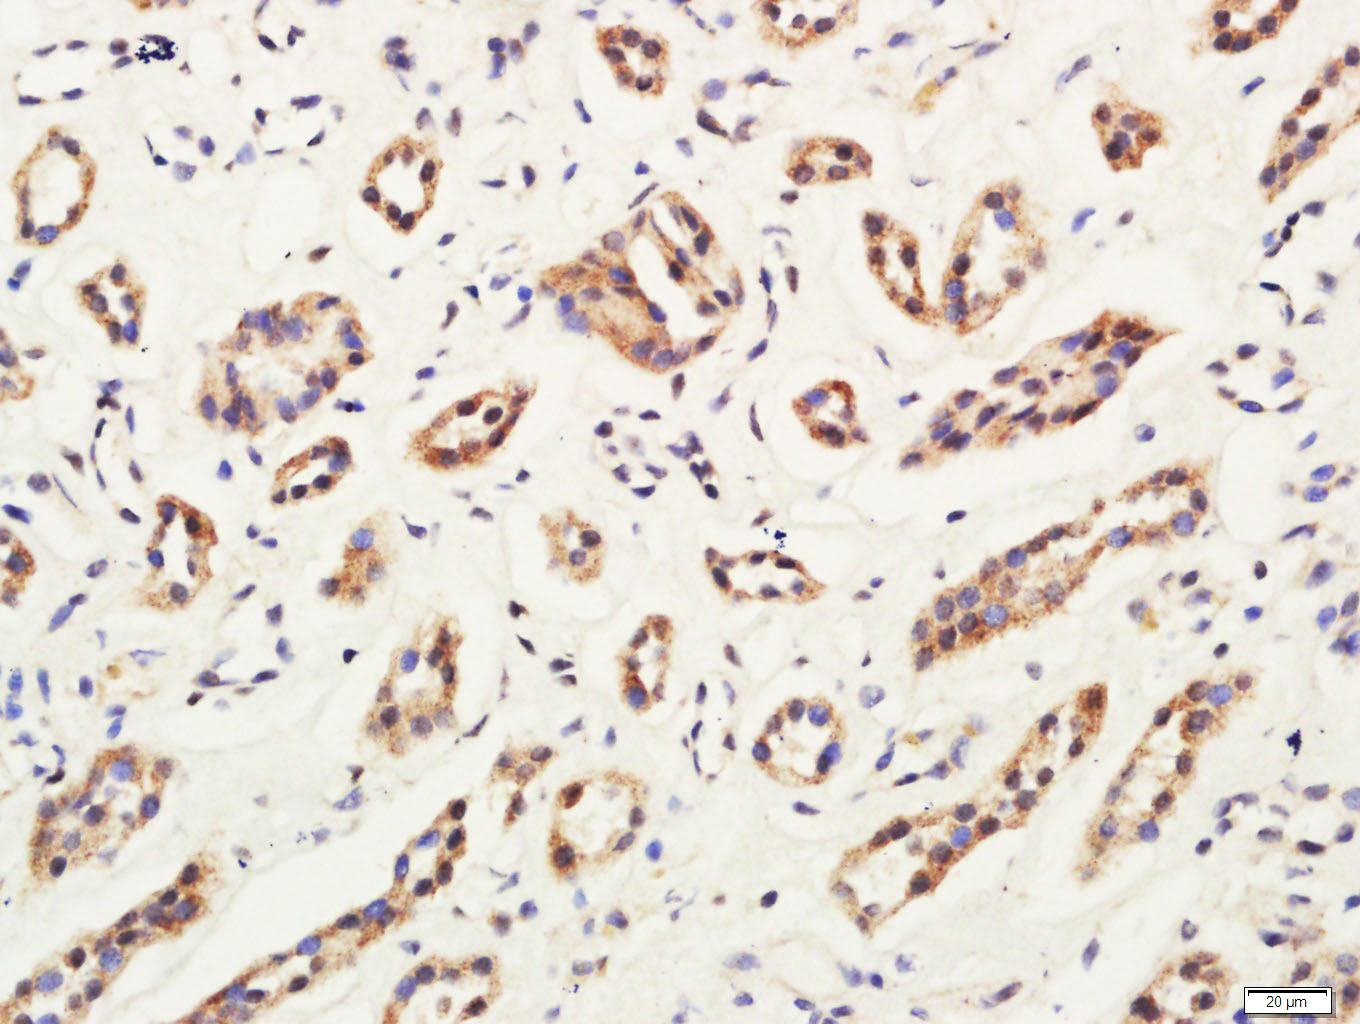

Tissue/cell: Rat kidney tissue; 4% Paraformaldehyde-fixed and paraffin-embedded; Antigen retrieval: citrate buffer ( 0.01M, pH 6.0 ), Boiling bathing for 15min; Block endogenous peroxidase by 3% Hydrogen peroxide for 30min; Blocking buffer (normal goat serum,C-0005) at 37∩ for 20 min; Incubation: Anti-C4orf52 Polyclonal Antibody, Unconjugated(bs-15196R) 1:5000, overnight at 4∑C, followed by conjugation to the secondary antibody(SP-0023) and DAB(C-0010) staining